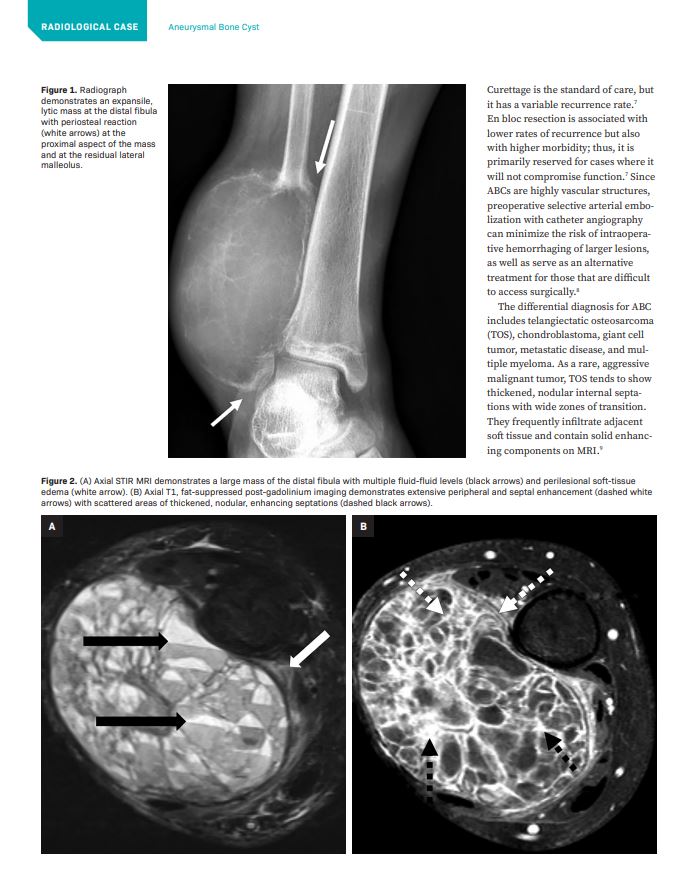

AppliedRadiology (@applied_rad) 's Twitter Profile Photo

Attention Medical Professionals! If you have an interesting radiology article or case, share it with us, you could get published! More👉bit.ly/3qDCpva #MedStudent #FutureRadRes #RadRes #RadFellow #Radiologist #AbRad #ERrad #BreastRad #IRad #VIR #NeuroRad #MSK #PedsRad

Attention Medical Professionals! If you have an interesting radiology article or case, share it with us, you could get published! More👉bit.ly/3qDCpva

#MedStudent #FutureRadRes #RadRes #RadFellow #Radiologist #AbRad #ERrad #BreastRad #IRad #VIR #NeuroRad #MSK #PedsRad